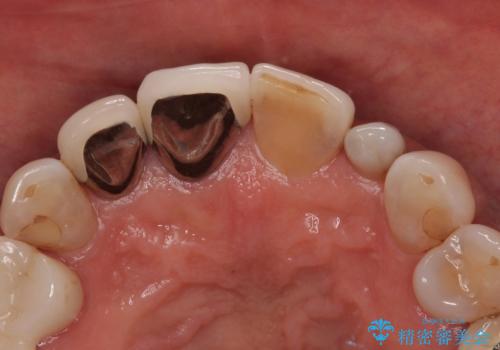

上顎前歯の歯肉ラインにエナメル質の欠損が認められ、そこが原因で冷たいものがしみている状態でした。

歯の大きさが小さいこと、隣の歯や反対側のセラミッククラウンの境目が見えていることなどから、前歯4本あるいは6本に対して、オールセラミッククラウンによる補綴治療をご提案しました。